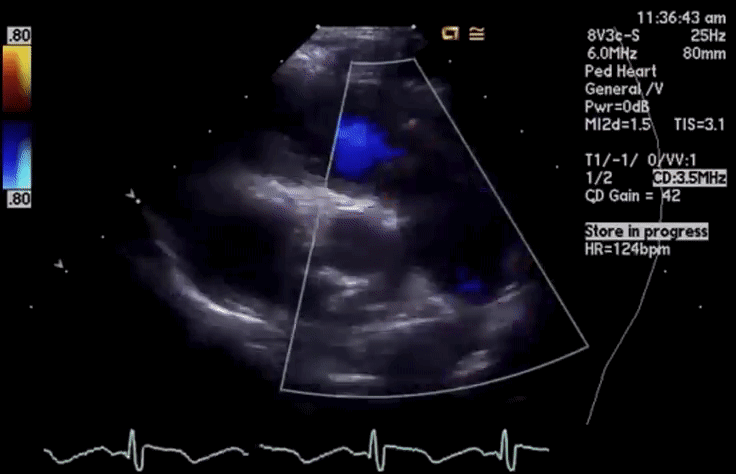

- Colour Flow Doppler 彩色血流

- Turbulence/aliasing 有无湍流 / 混叠现象

- Site of turbulence helps placement of Doppler cursor 湍流位置及方向有助于放置多普勒取样线,进行最大血流速度的描绘

- Associated regurgitation 伴反流

在 2D 下如果见到了肺动脉瓣增厚或穹隆样改变,可以加上彩色血流。彩色血流图可以看到湍流,在放置 CW 或者 PW 时,可以使取样线对齐湍流的方向,以获得最大速度来确定狭窄的程度

舒张期也可以观察有没有肺动脉瓣反流,若存在,也需要评估和分析

# Pulmonary Regurgitation (PR)

- Diastolic jet in the RVOT 右室流出道中的舒张期血流

- Jet length >10 mm 射流长度 > 10 毫米

- Physiological vs pathological PR: duration of flow ie holodiastolic

生理与病理 PR: 血流持续时间,即全舒张期 - Jet width: wider jets worse; evaluate at jet origin "vena contracta" [2]

射流宽度:较宽的射流更糟;在反流起始处评估缩流颈宽度 - Severe PR: jet width vs RVOT width > 55-65%

严重 PR: 射流宽度 vs RVOT 宽度 > 55-65% - Detection of flow reversal in pulmonary arteries

肺动脉血流逆转的检测